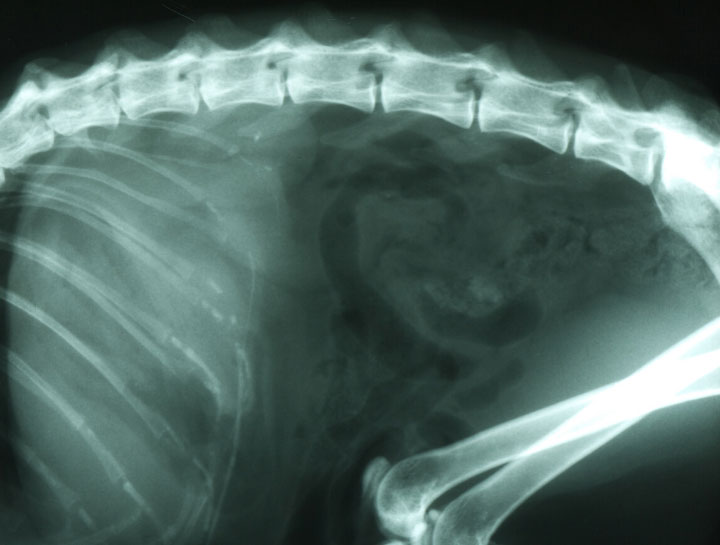

Pet Digital Radiology

Digital x-rays assist in diagnosing illness & injury.